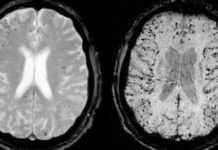

As indicated by a June 2014 article included in The Independent (UK), a noteworthy report directed by analysts at the Karolinska Institute in Sweden...